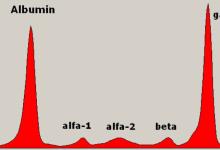

Two literature reviews show that SLE patients with an increased risk of PRES are more likely to be younger females, hypertensive, with renal insufficiency, active disease, lymphopenia, and hyperlipidemia. (Citation source http://buff.ly/1WduDzl)